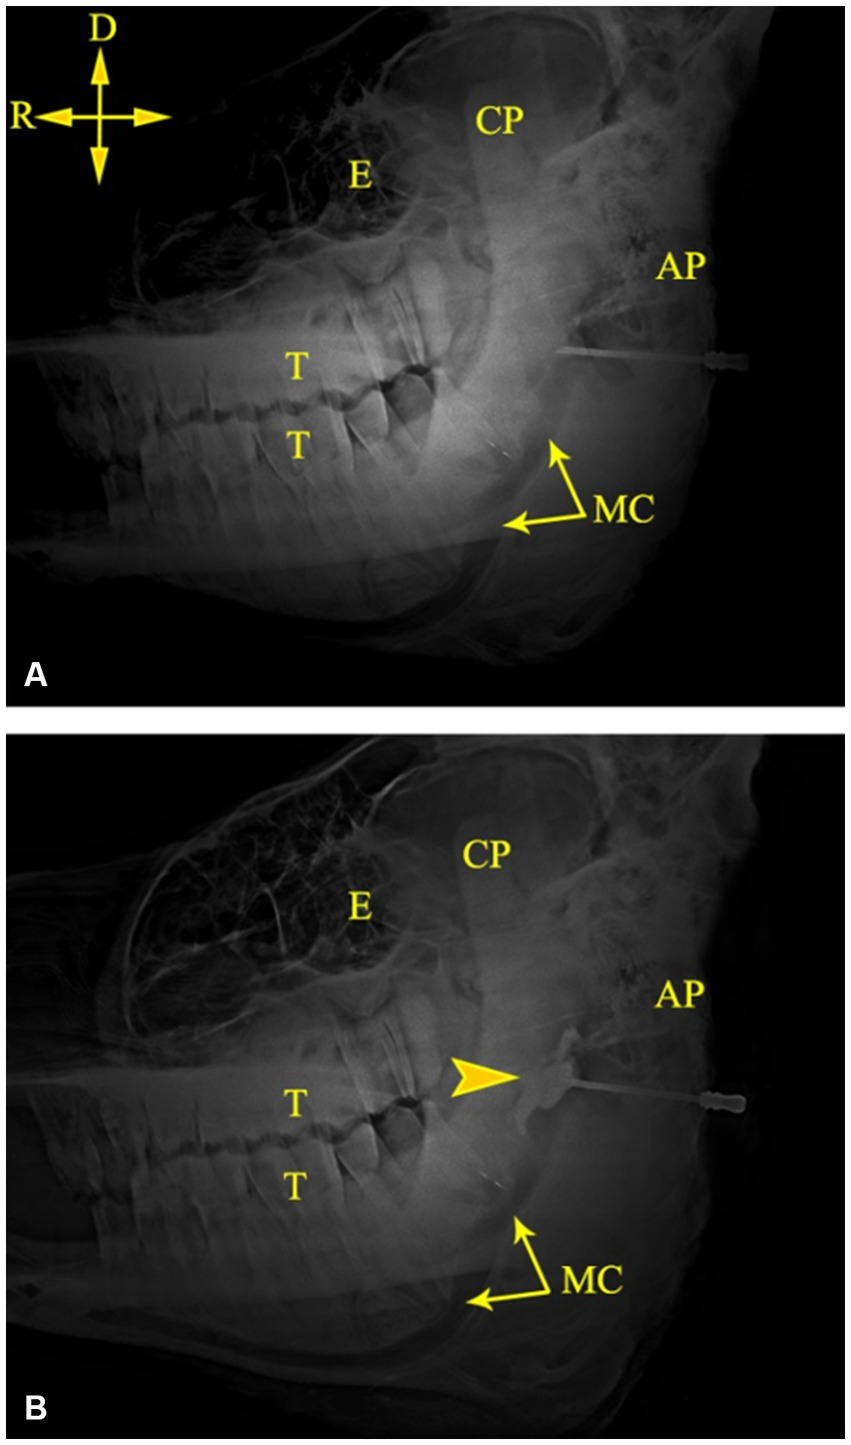

Figure 3

The mandibular canal could be easily recognized on radiographic images of camel heads owing to its radiolucent tubular appearance along the ventral border of the mandible (Figure 4). Combining measurements M3 (from the MF to the caudal border of the mandible) and M8 (from the MF to the highest point of the angular process) with the abovementioned scheme achieved perfect localization of the MF on radiographs of the injected heads, where the injected contrast agent was observed at the entrance of the canal soon after its injection (Figure 4). Additionally, radiographic imaging of the cadaver heads revealed successful placement of the contrast agent at the entrance of the mandibular foramen in all tested specimens. Needle placement at the level of the MF was easily recognized, and the contrast agent adequately infiltrated the area around the mandibular nerve.

Figure 4

Lateral radiographs of the left side of a camel head showing the tip of the needle at the MF (A) and successful deposition of the contrast medium at the MF (B). AP, angular process; CP, coronoid process; E, Eye; MC, mandibular canal; T, cheek teeth. Directions are dorsal (D) and rostral (R).